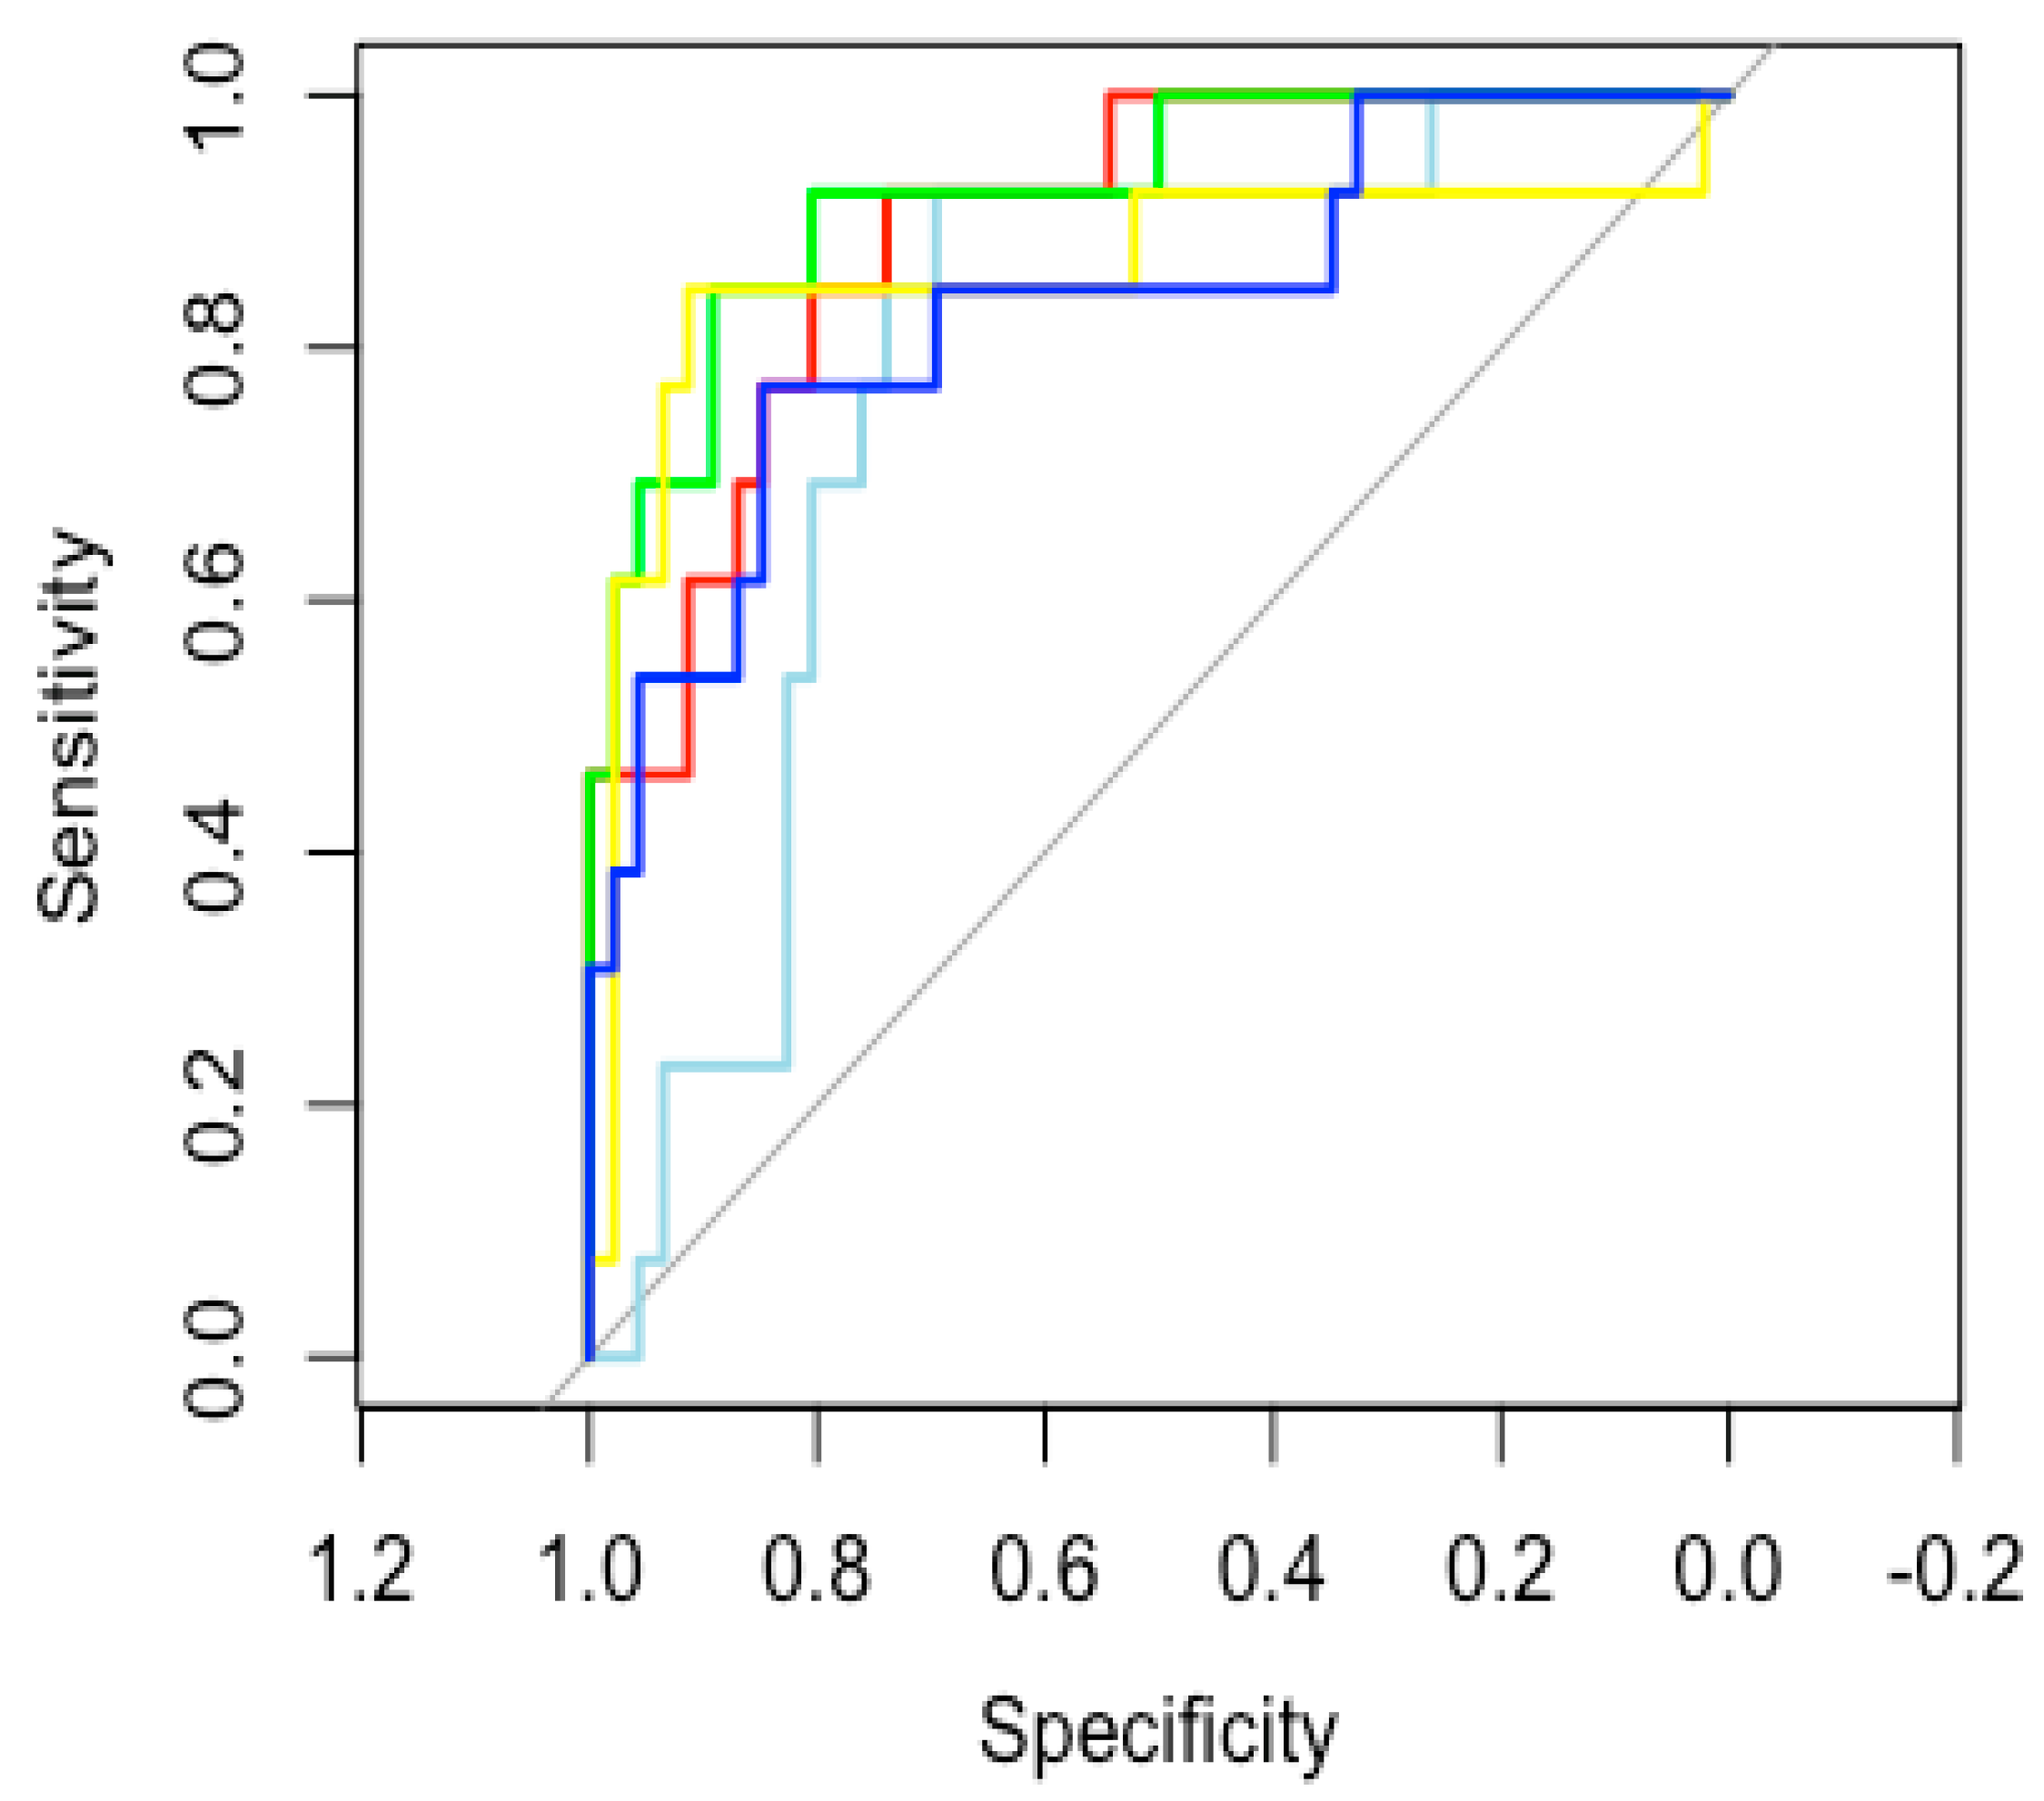

3.4. Model Accuracy Estimation

3.5. SMOTE Analysis